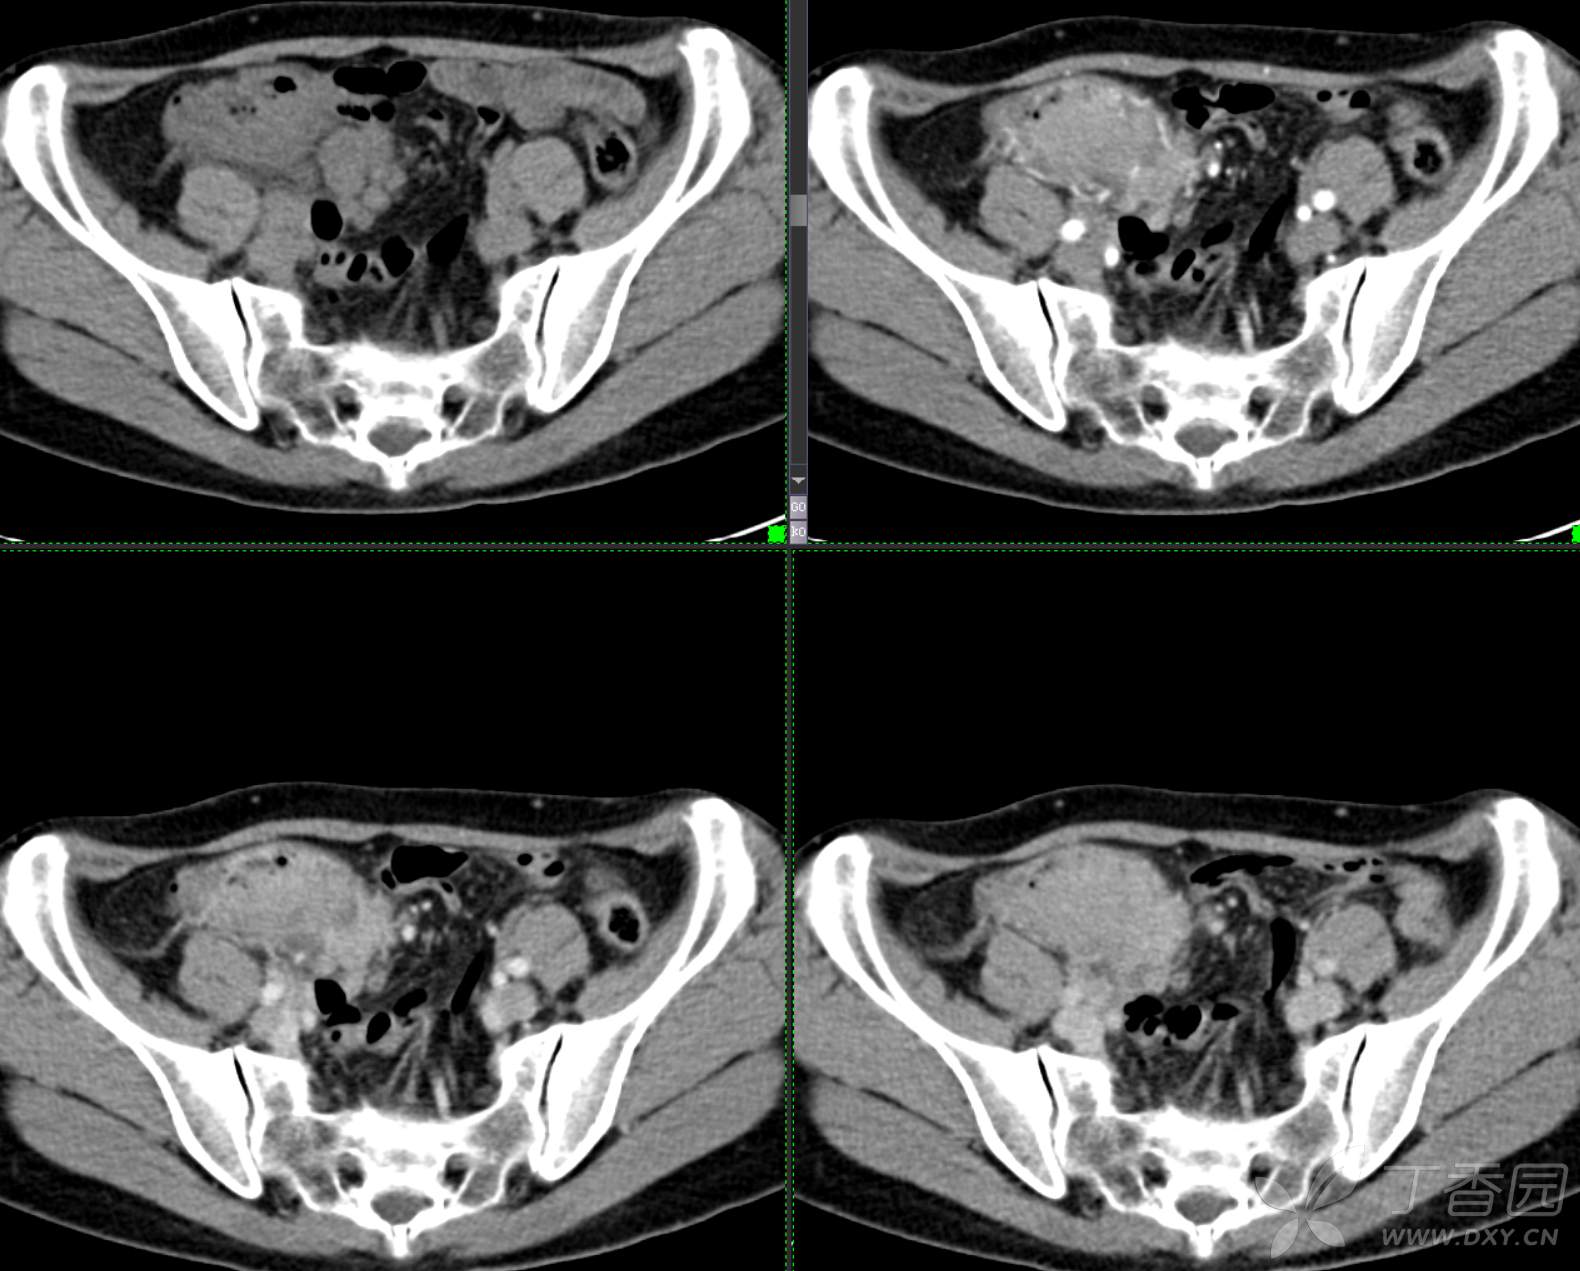

腹组13:患者,女,62岁,大便习惯改变2月余

主 诉: 【大便性状改变2月余】

现病史: 患者2月余前无明显诱因下出现大便次数增多,无明显血便黑便及粘液脓血便,大便次数由1次/日增加至2-3次/日,大便形状变细如小指,偶稀软不成形,无腹痛腹胀腹泻,无恶心呕吐、胸闷气促,肛门排气通畅,无发热盗汗。至当地医院就诊,行肠镜检查发现"回盲部占位"。为进一步治疗,我院门诊拟"回盲部肿瘤"收住入院。